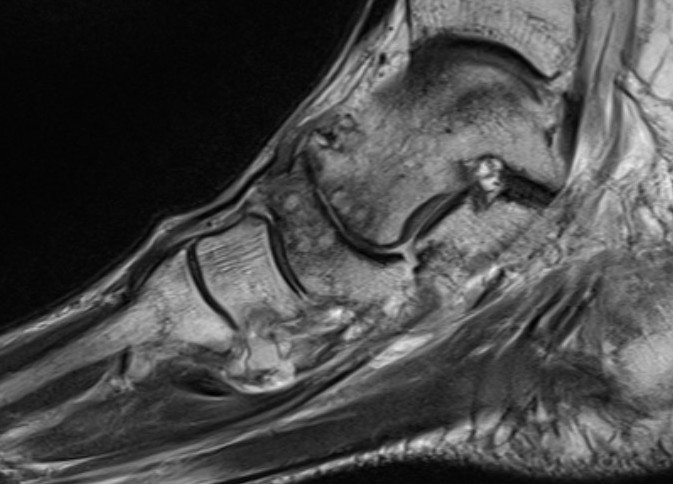

MRI